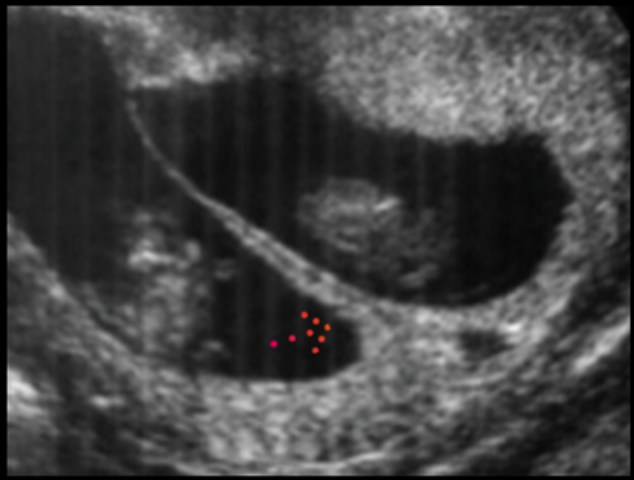

USG obstétrico

Qual é o sinal ecográfico apresentado na seta e o que indica?

Sinal do Lambda

Presentes em gestações dicoriônicas - identificação de septo espesso entre os sacos gestacionais, presença de duas placentas separadas ou por gêmeos de sexos discordantes